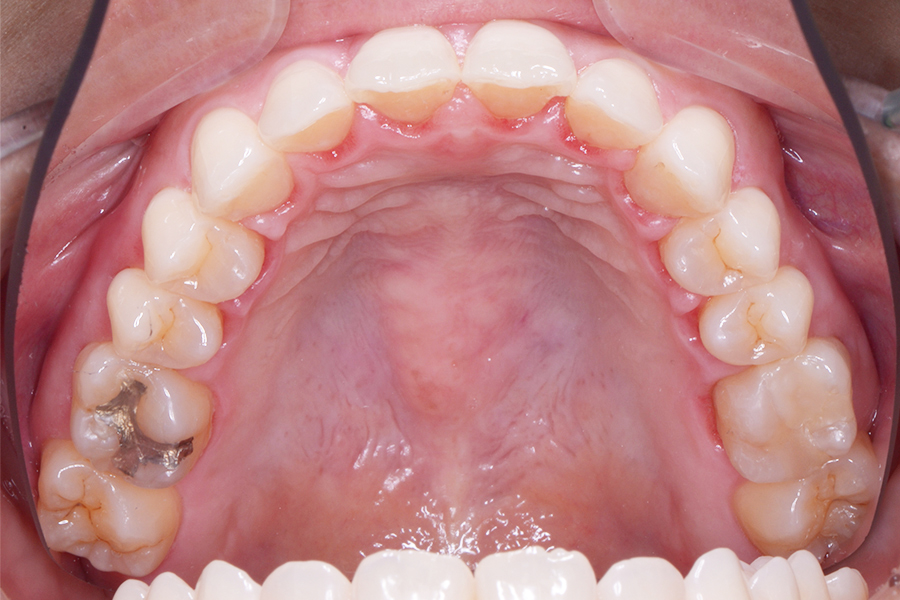

【40代女性】

真ん中二本の捻じれた歯を

治したい

• 治療後

主訴 真ん中二本の捻じれた歯を治したい

期間 治療期間8か月

費用 治療費35万(別途調整料)

※デンタルローン120回 ¥3,300/月

治療内容 上顎リンガル矯正(裏側矯正)

治療に伴うリスク 後戻り